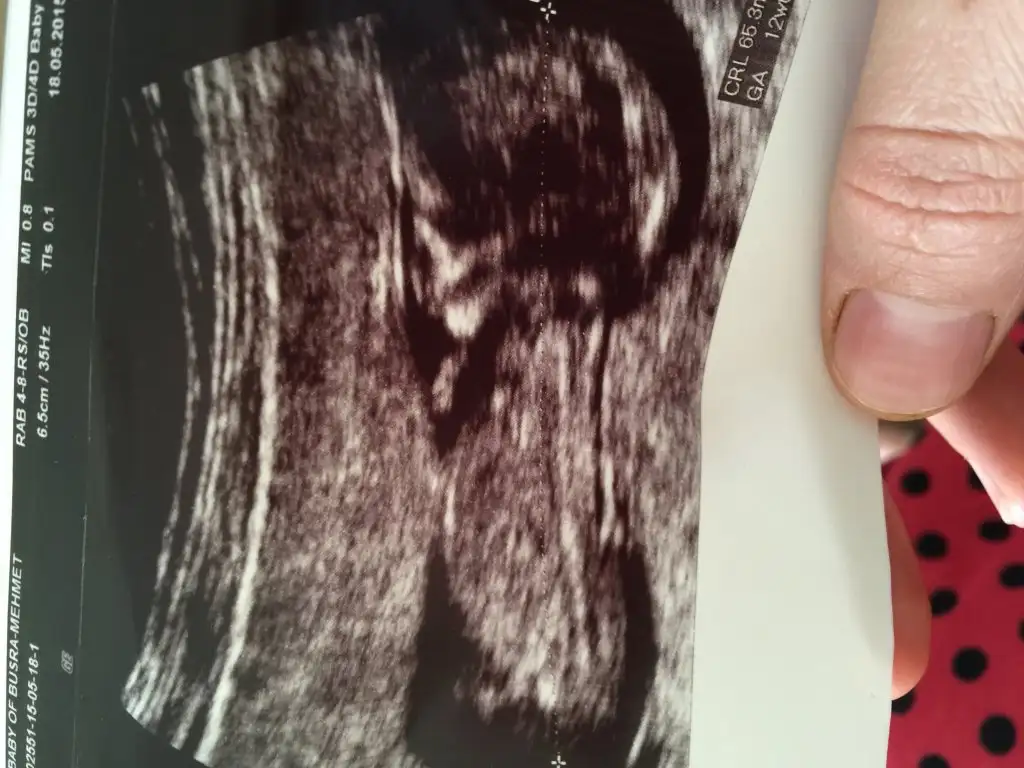

Arkadaşlar bana da yorum yaparmisıniz mnormalde 10+3günlükken gitmiştim dktr.ama bebişim bir hafta ileri gösteriyor yani burda 11+2 günlük..Allah varya yukarda gönlümden erkek geçiyor çünkü 2 kız ım var ama tabi hayırlısı..

Rabbim hayırlısıni inş.gönlümüzün isteğiyle verir canım mariamelikem sanki seninki erkek mi yukarı bakan bi çıkıntı var gibi

Canım kordonunun hemen altında bir çıkıntı daha var. Yukarı açılı duruyor. Bu erkek bebek nubudur. Eğer görüntüden kaynaklanan bir sıkıntı yoksa bence bu bebek erkek. Çünkü nubu o kadar Yukarıdan başlayıp, yukarı açılı olan ancak erkek bebek olabilir :) ayrıca neye göre kesin kız dedi ki?